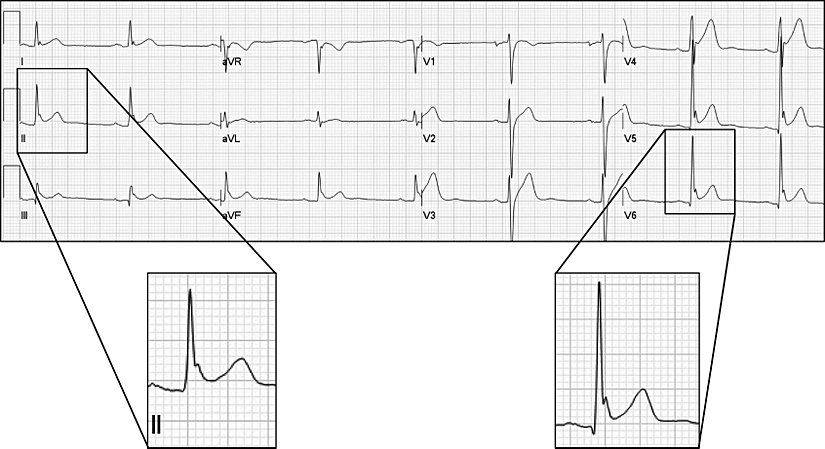

Kalpteki ileti sistemi bozuklukları, örneğin kalıtsal Wolff Parkinson White sendromu (PRKAG2 gen mutasyonu), konjenital uzun QT sendromu (KCNQ1, KCNQ2 ve SCN5A gen mutasyonları), Brugada sendromu (SCN5A gen mutasyonu) AKÖ ile yakından ilişkilidir. Kalpte iletim sistemindeki bozukluklar sonucu ventriküler taşikardi ya da hızlı ve düzensiz şekilde uyarılan ventriküllerin senkronize kasılma fonksiyonunu kaybederek "kalp titremesi" şeklinde tasvir edebileceğimiz ventriküler fibrilasyon gelişebilir ki bu da defibrilasyon yapılmazsa ölüme neden olabilir. Atletler ve sporcularda gördüğümüz aniden ölümlerin artmış efor durumlarından meydana gelen ritmik bozukluklar ile ilişkisi vardır.

Çoğu vaka geliştiği andan itibaren 1 saat içinde, hatta bazen isminin hakkını fazlasıyla verecek şekilde çok hızlı ölüme neden olur. Yeterli zaman diliminde tanı için hastalık öyküsü, anamnez, EKG, Holter monitörü ile değişiklikleri takip etmek hatta koroner anjiyografi uygulanması gerekebilir.